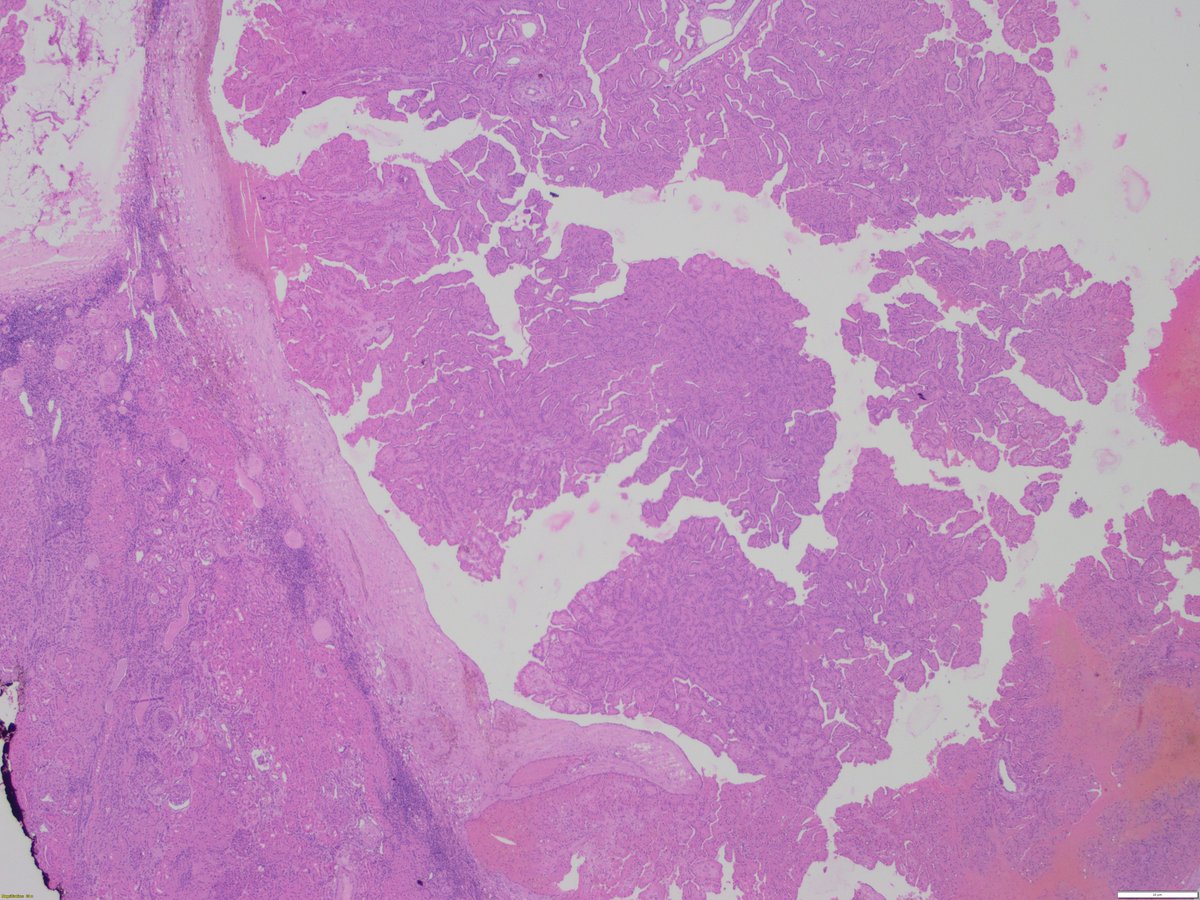

May 2023 is #bladdercancerawarenessmonth Urothelial carcinoma can invade the prostate, mimic high grade #prostatecancer & occasionally be sampled on needle biopsy (see PICS) #gupath